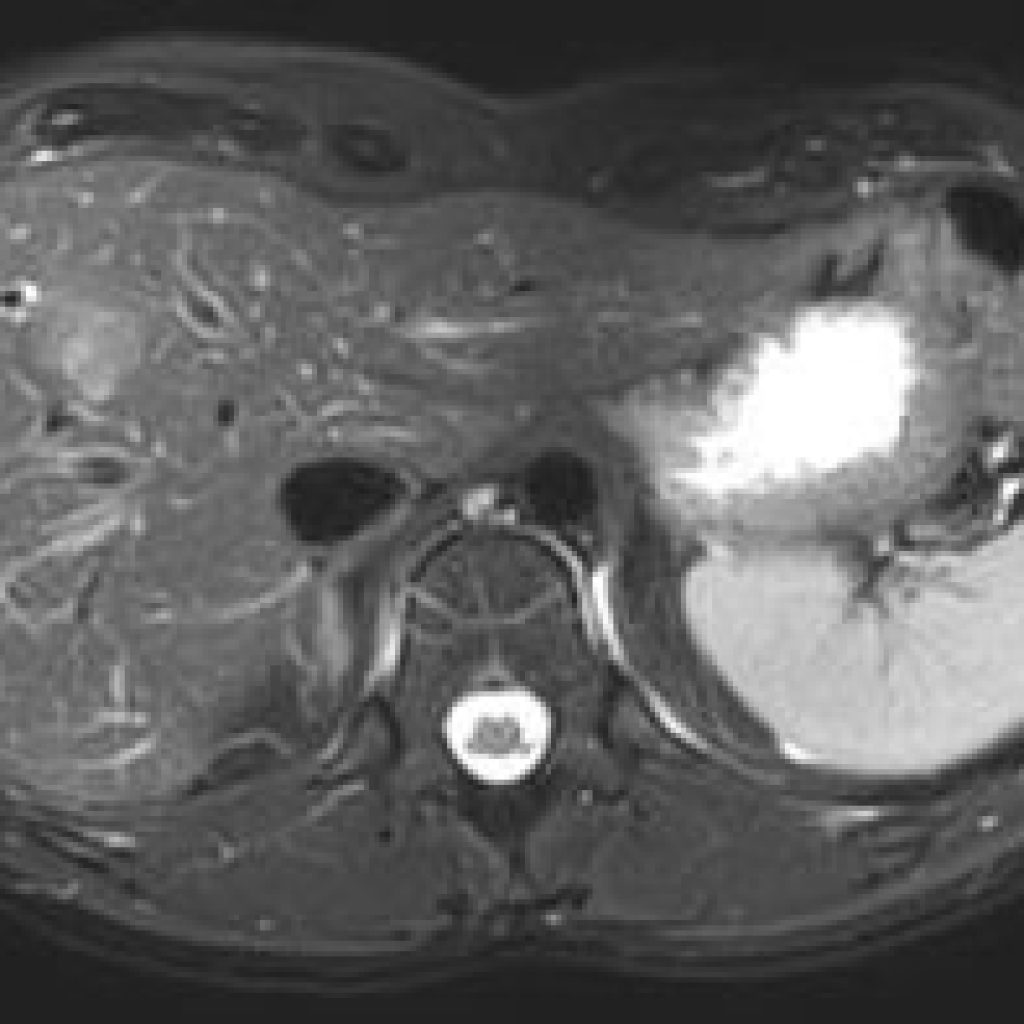

Ce type d’exploration s’intéresse au foie, aux surrénales, aux reins, au pancréas, à la rate et au péritoine

Quelques exemples :

– recherche d’une surcharge en fer du foie,

– quantification d’une stéatose, suivi des fibroses intra-hépatiques,

– cartographie des lésions cancéreuses et suivi de leur réponse sous traitement,

– recherche de calculs au sein des voies biliaires ou de la vésicule.